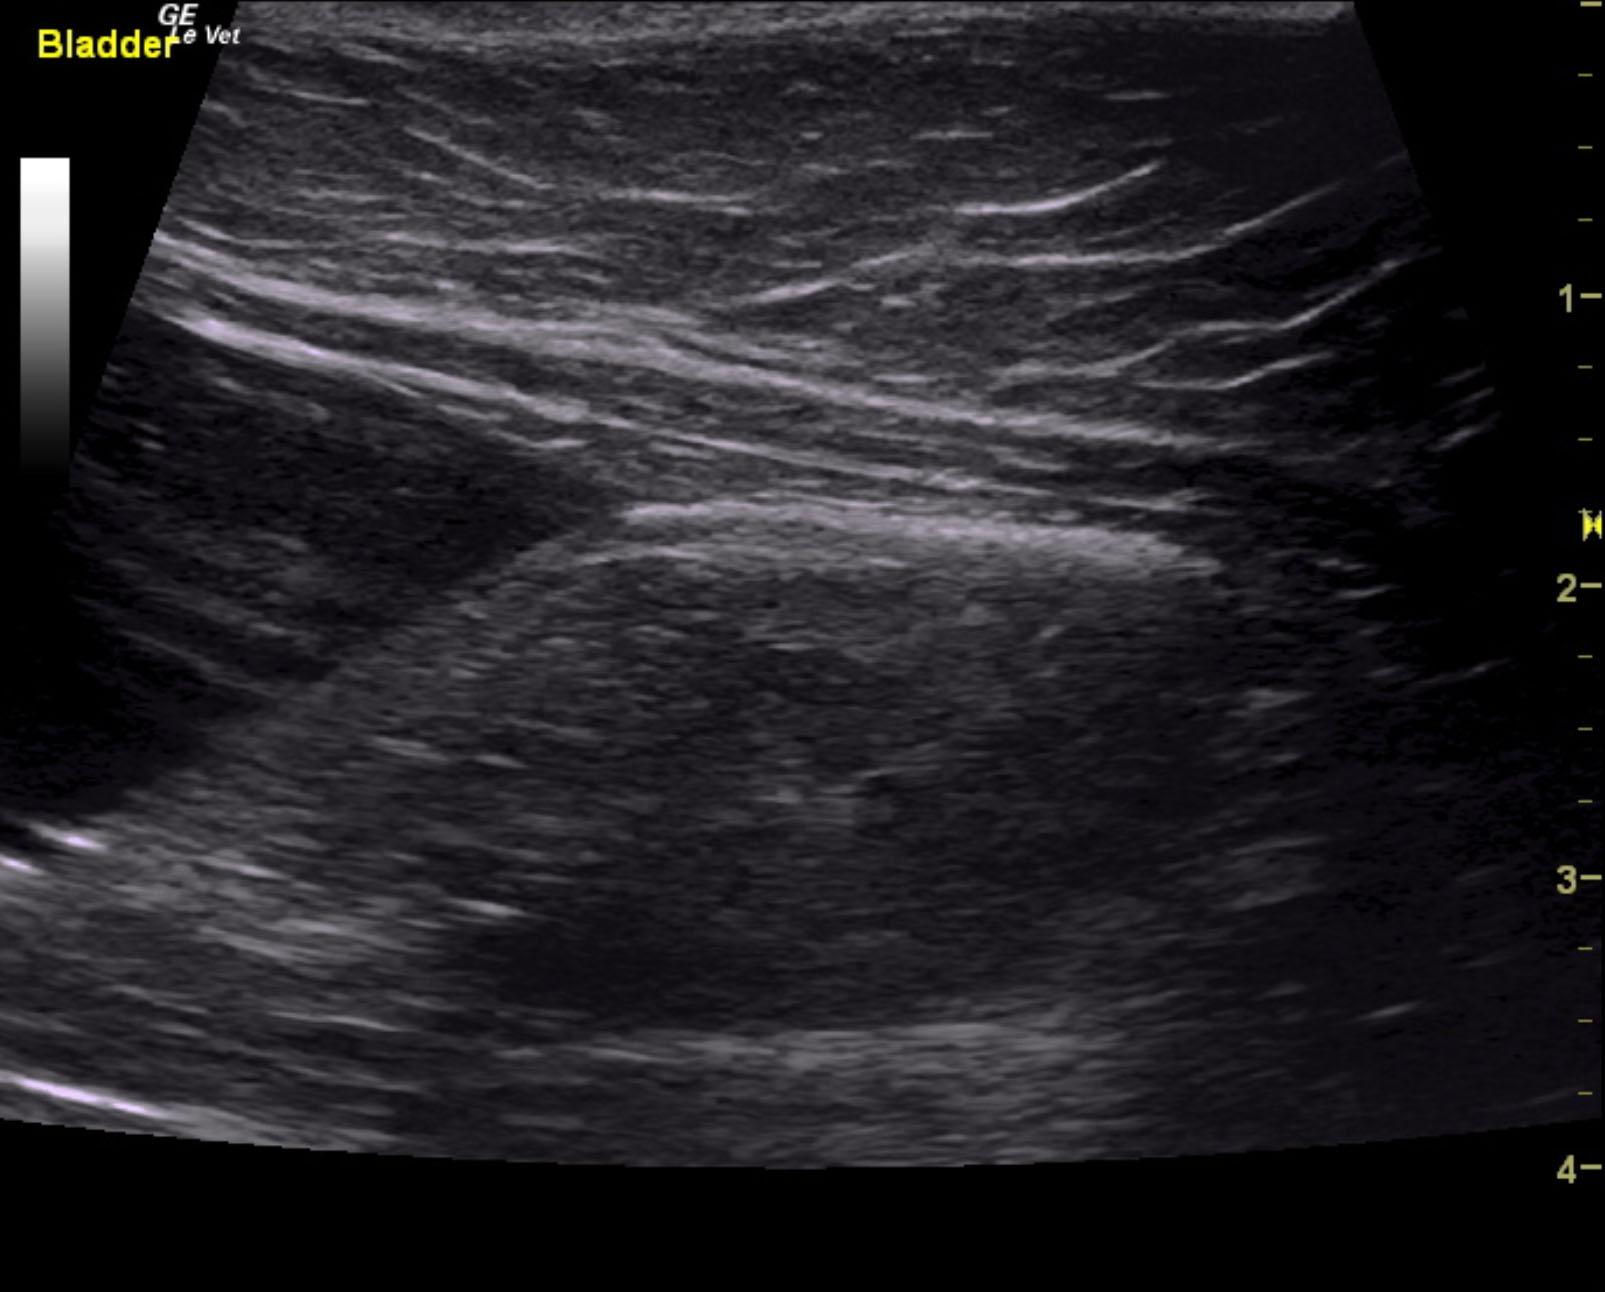

A 5-year-old NM DSH was presented for evaluation of weight loss and a 5-day history of decreased appetite and lethargy. On physical examination 8% dehydration, pale mucosa, and a full but easily expressible bladder were present. Abnormalities on CBC and serum biochemistry were mild lymphopenia and neutrophilia, azotemia (BUN >180, creatinine >20), and hypoproteinemia. Survey radiographs showed irregular kidneys with opacities and possible opacities within the urethra.